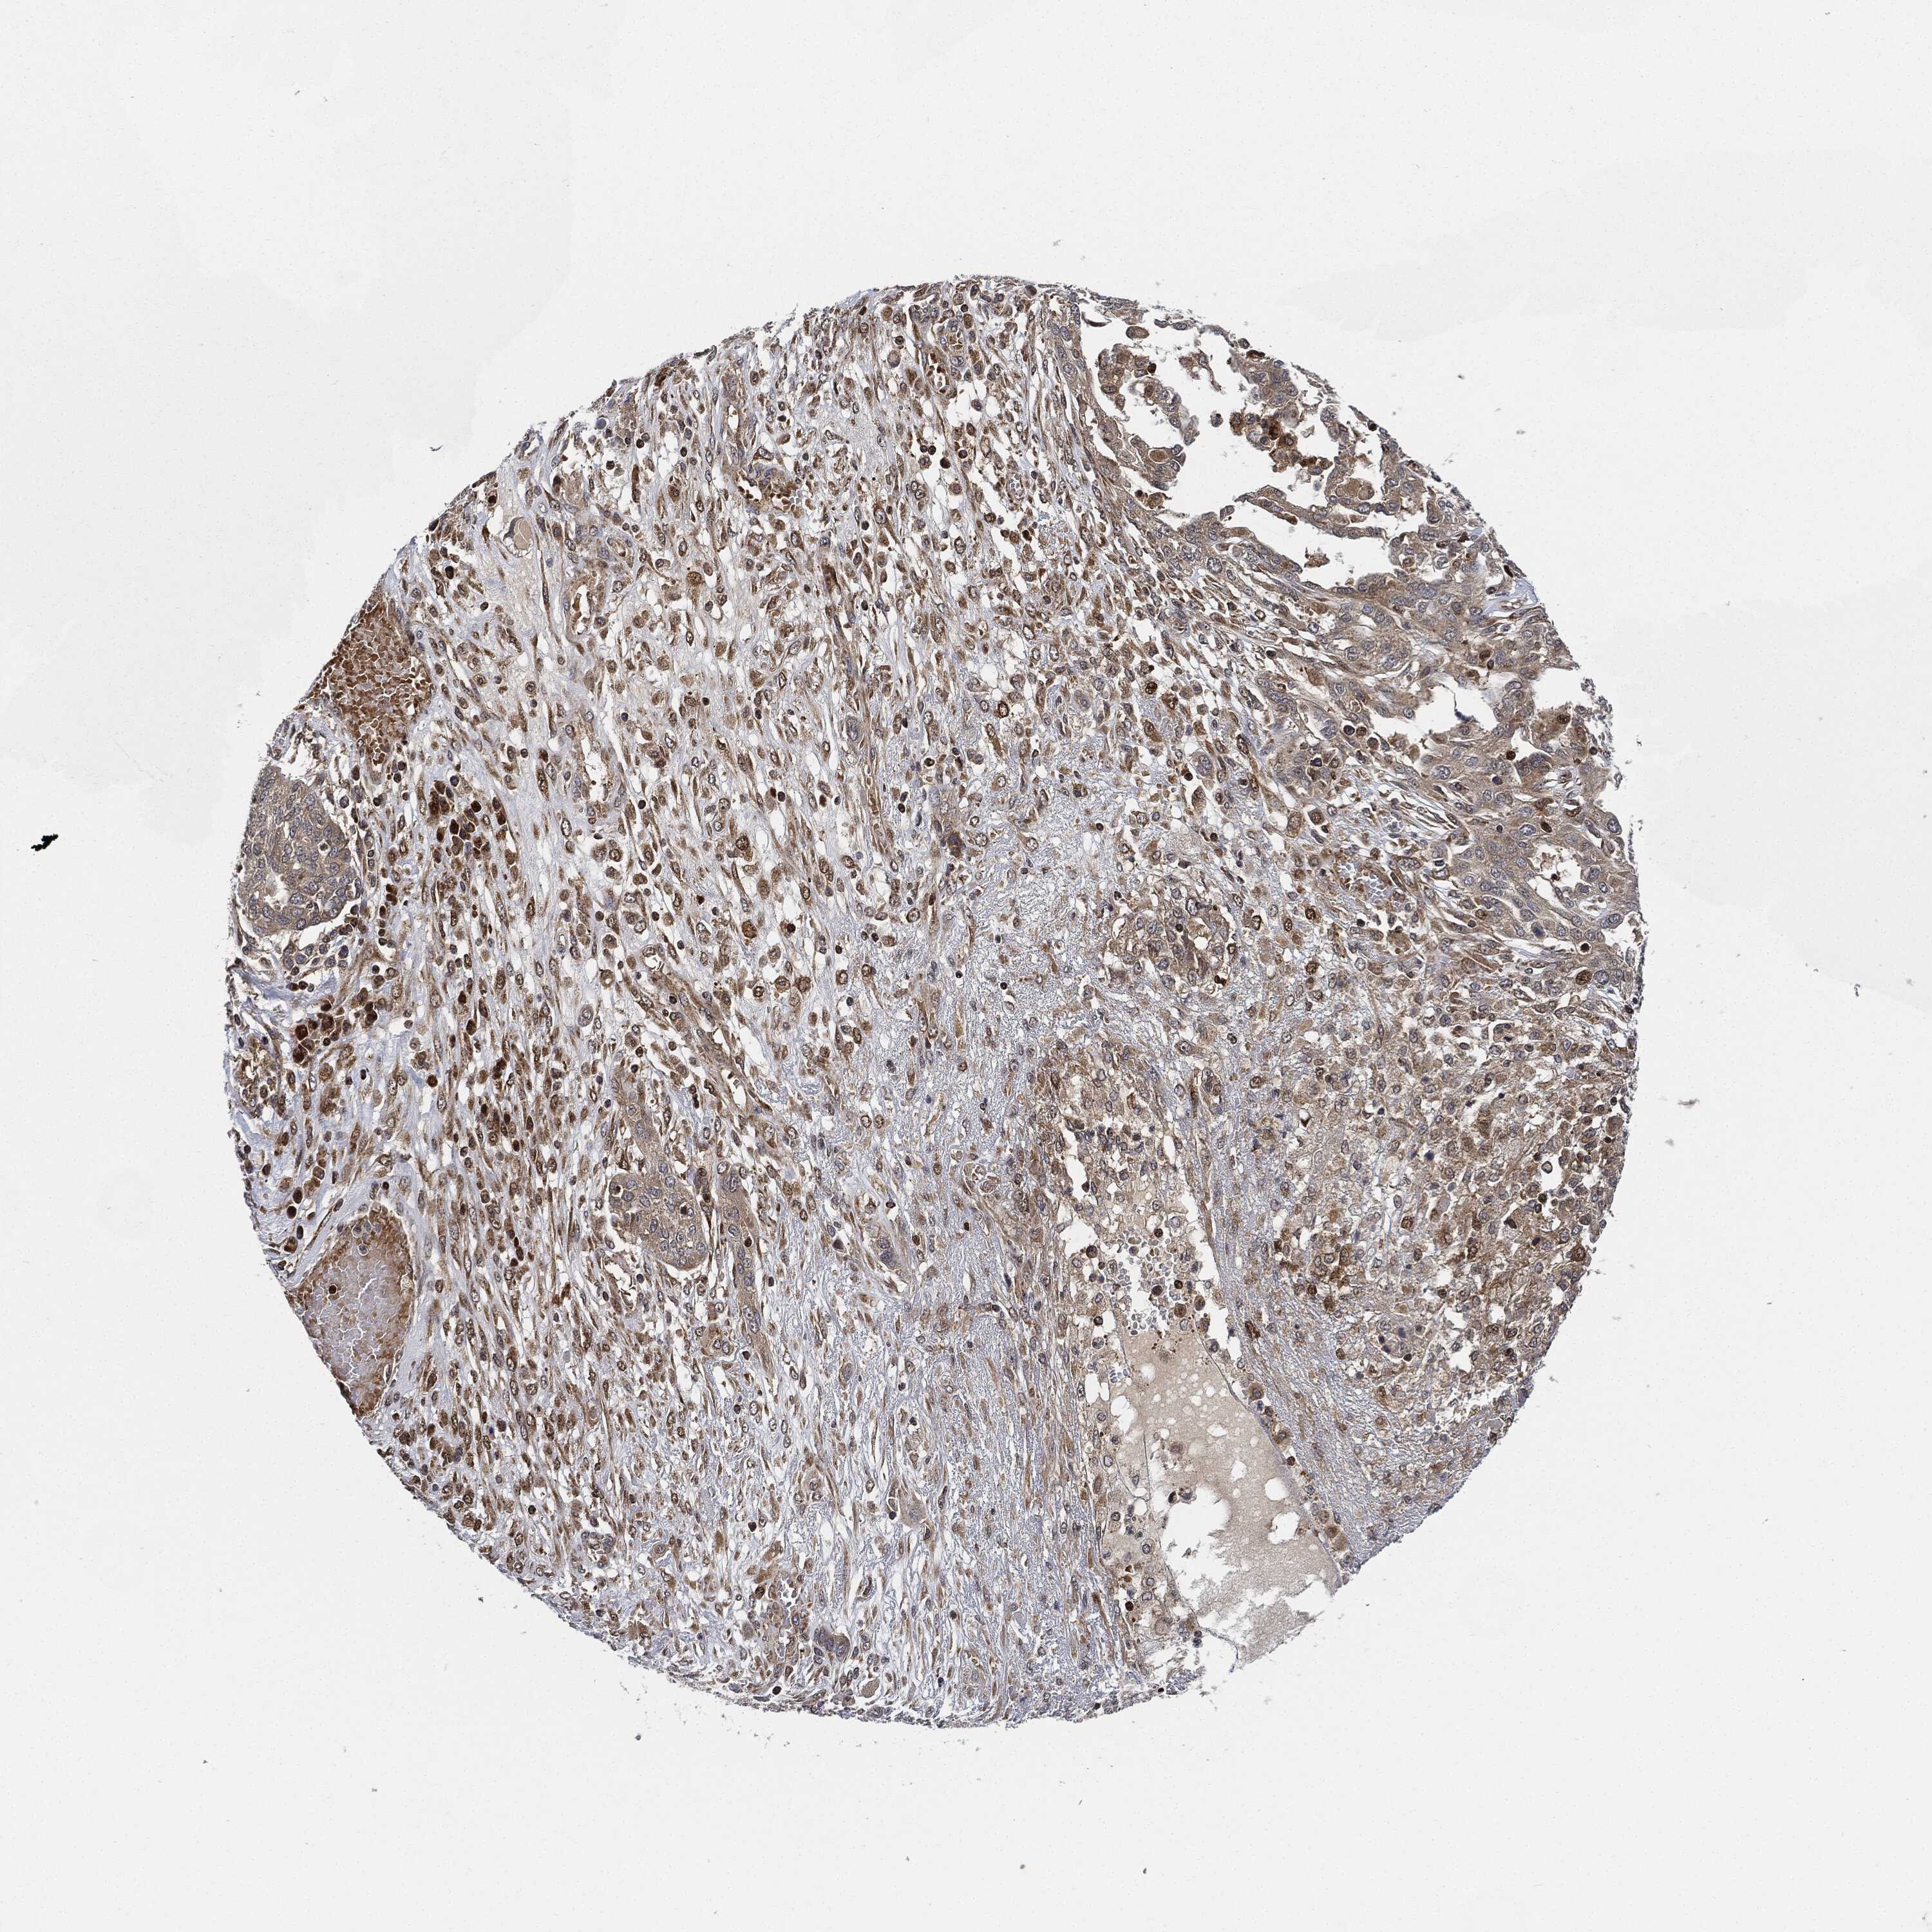

OVARIAN CANCER - Protein expressioni

A mouse-over function shows sample information and annotation data. Click on an image to view it in a full screen mode. Samples can be filtered based on level of antibody staining by selecting one or several of the following categories: high, medium, low and not detected. The assay and annotation is described here.

Note that samples used for immunohistochemistry by the Human Protein Atlas do not correspond to samples in the TCGA dataset.

Antibody stainingi

Antibody staining in the annotated cell types in the current human tissue is reported as not detected, low, medium, or high, based on conventional immunohistochemistry profiling in selected tissues. This score is based on the combination of the staining intensity and fraction of stained cells.

Each image is clickable and will lead to virtual microscopy that enables deeper exploration of all samples and also displays staining intensity scores, fraction scores and subcellular localization as well as patient and tissue information for each sample.

Antibody HPA002633

Carcinoma, endometroid

Cystadenocarcinoma, serous, NOS

Cystadenocarcinoma, mucinous, NOS

Carcinoma, NOS